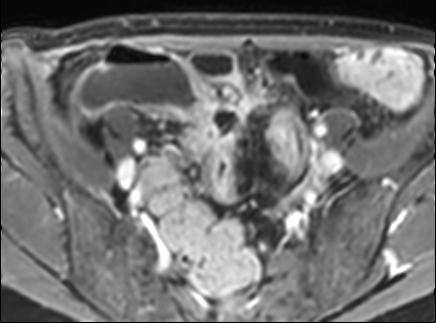

Rò

Đường xoang và đường rò là các biến chứng thường gặp ở bệnh nhân mắc bệnh Crohn.

Cả hai đều ngấm thuốc rõ rệt trên chuỗi xung T1W sau tiêm gadolinium.

Đường rò có thể biểu hiện dưới dạng cấu trúc phân lớp kiểu ‘đường ray tàu hỏa’ hoặc như một cấu trúc tuyến tính ngấm thuốc.

Đường rò có thể đi từ quai ruột này sang quai ruột khác, đến một tạng rỗng khác hoặc ra da.